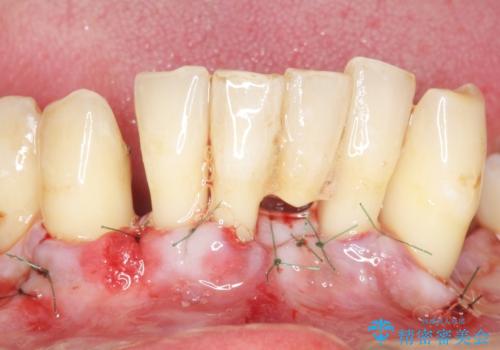

精査したところ、全顎的な重度の歯周病により下顎前歯に激しい動揺を認めました。

できるだけ自分の歯を残したいという患者様の強いご希望により、禁煙指導後再生療法(骨を増やす手術))を行いました。

再生療法から1年後リエントリー手術により骨の再生を確認し、骨外科処置(骨を平らにして歯周ポケットの根本的な改善を図る処置)を行ったのち、連結補綴を行いました。

再生療法と骨外科処置により、歯周ポケットは全周2mm以下に改善されました。